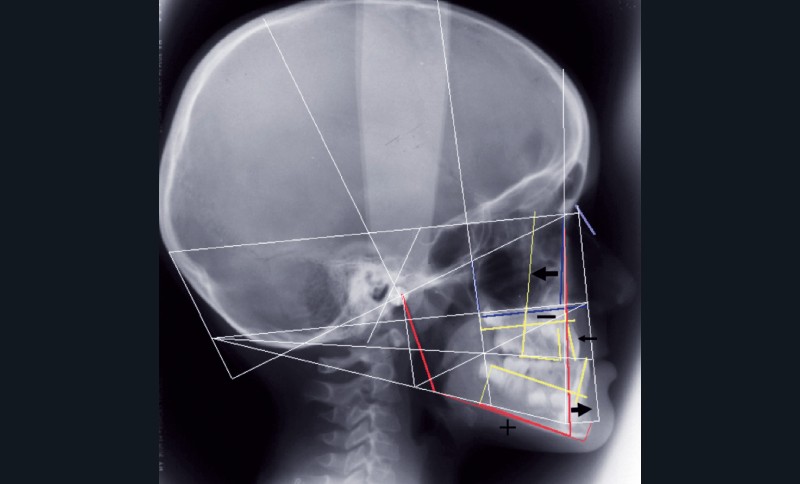

Le bilan radiographique (fig. 6) par l’analyse architecturale de Delaire et l’analyse dento-squelettique confirme l’examen clinique et conduit au diagnostic radiologique suivant :

• pas de prédisposition de la base du crâne à la classe III,

• rétromaxillie,

• brachymaxillie avec petite brachyprémaxillie,

• linguoversion incisive maxillaire,

• légère prognathie mandibulaire par dolichocorpie.